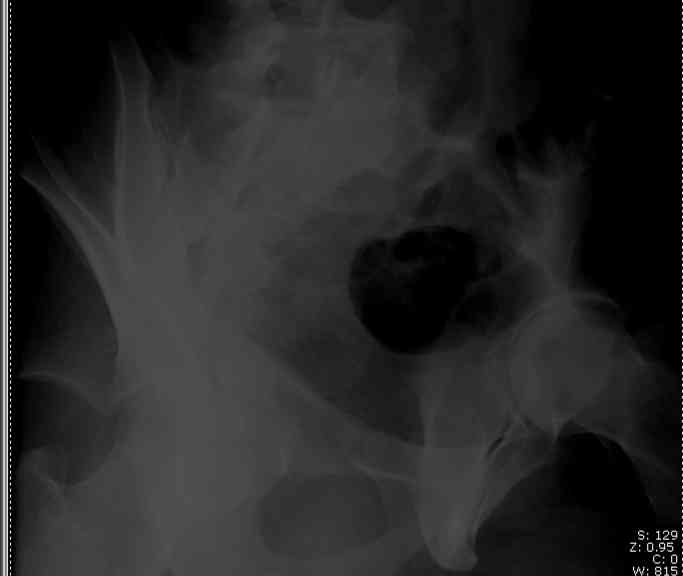

the case that I found is a 20yo male, MCC. his AP pelvis shows an interesting position of his bladder. it is pushed aside by a hematoma from SGA injury. we did a limited lateral window approach for the anterior column first, pt bumped up/supine. then closed and repositioned for KL. I could not find intra-op photos of cases when we did only a small incision for the AC screw (but they do exist!!). the lateral window is available for reduction assessment if a KL approach is being used. in the lateral position this window is available. the prone position definitely takes pressure off of the post column and facilitates reduction. in the lateral position a schantz pin in the ischial tub +/- bone hook in sciatic notch helps with PC reduction. the lateral position also gives better airway access for anesthesia. airway problems are rare, but prone position seems to be a bit more of a challenge to exchange the tube, or reintubate altogether. just something further to debate!